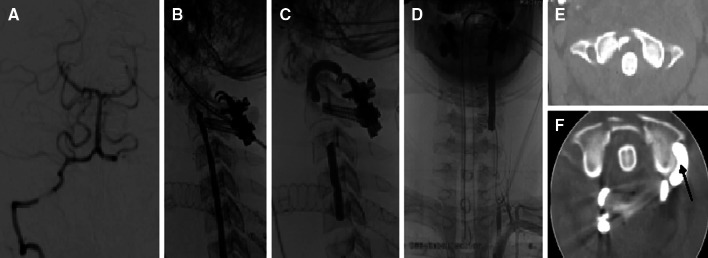

Fig. 1.

A 16-year-old male after a traffic accident, initial GCS 7, tetraplegia and priapism. a Initial right vertebral angiogram shows a VA occlusion with retrograde filling of the left V4 segment and PICA, intraoperative with aspect of left-sided VA transection. b Postoperative lateral angiogram of the left VA shows high grade stenosis at the C1–C2 level. c, d The left vertebral artery was occluded with two detachable silicone balloons e: CT before atlanto-axial fixation (C2 pedicle screws and atlas clamp) f postinterventional CT (arrow detachable balloon within atlas loop)